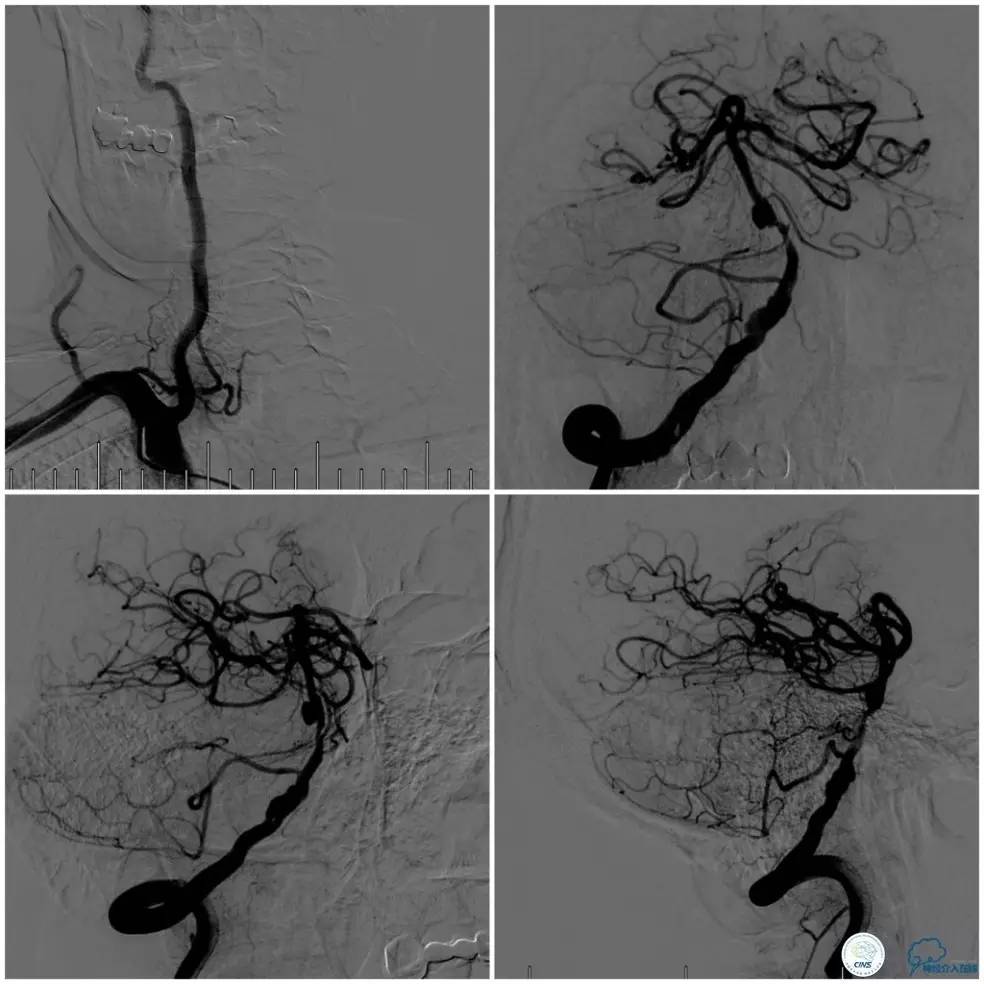

术前DSA:基底动脉中段狭窄,狭窄远端动脉瘤,右椎动脉优势,右椎V4段管壁不光滑(图7)。

图7

左椎动脉V3段以远未见显影(图8)。

图8

前循环未见明显向后循环代偿(图9)。

图9